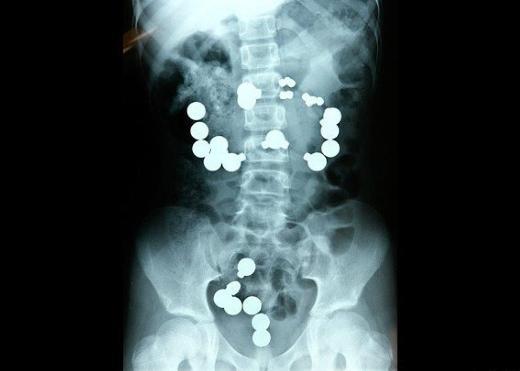

4. ABD'nin Raleigh kentindeki hapishaneden gelen bu röntgenlerde ise mahkumların hapishaneden çıkıp hastaneye yatabilmek için vücutlarına yatak yayı gibi metaller soktukları görülüyor.

ABD'nin Raleigh kentindeki hapishaneden gelen bu röntgenlerde ise mahkumların hapishaneden çıkıp hastaneye yatabilmek için vücutlarına yatak yayı gibi metaller soktukları görülüyor.